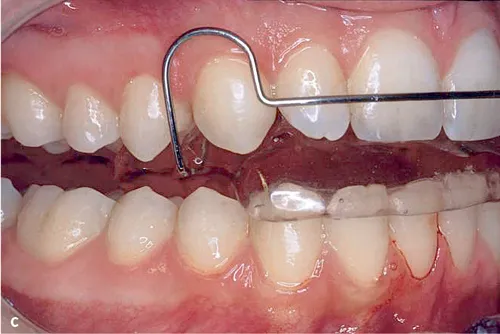

Abb. 3a bis c Intraorale Fotos von drei Aktivator-Patienten mit unterschiedlich hohen Konstruktionsbissen: a) Niedriger Konstruktionsbiss (2–4 mm)1, b) hoher Konstruktionsbiss (15–20 mm)10 und c) mittelhoher Konstruktionsbiss (5–7 mm)11.

3.Bei einem mittelhohen Konstruktionsbiss (5–7 mm), 1 bis 2 mm außerhalb der Unterkiefer-Ruheschwebelage (Abb. 3c), können sowohl die myostatische Reflexaktivität als auch die vergrößerte tonische Muskelspannung wirksam sein11. Der mittelhohe Konstruktionsbiss wird vor allem in Europa verwendet.